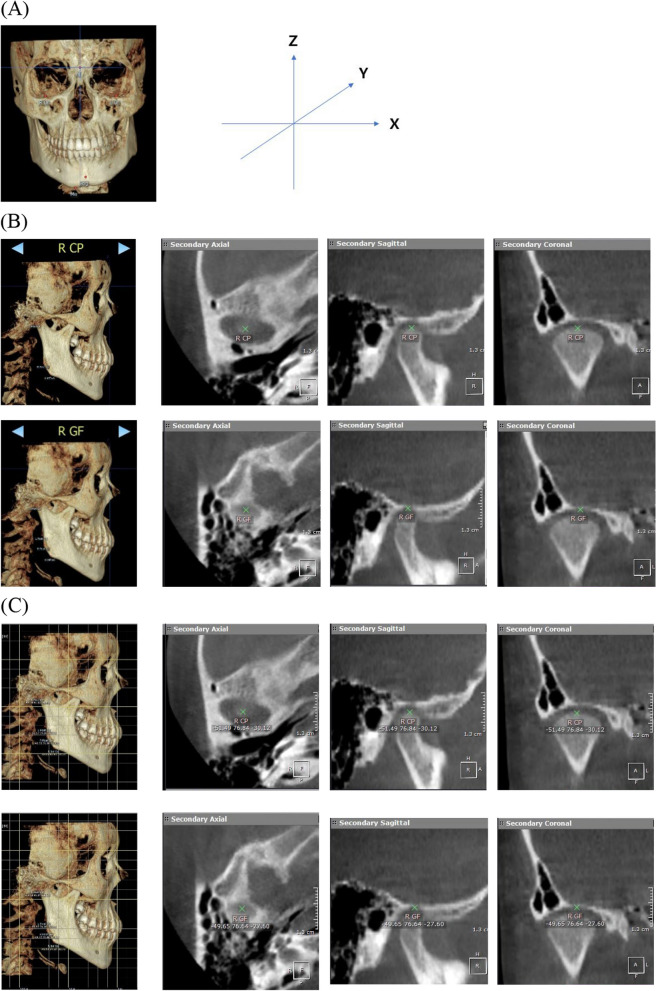

Methods: This retrospective study included 31 patients with unilateral mandibular condylar fractures treated non-surgically at the Ajou University Dental Hospital between 2005 and 2023. Computed tomography was performed at the time of the fracture (T 0) and > 6 months after non-surgical treatment (T 1). The extent of recovery of the highest point of the condyle head was measured in three-dimensional x-, y-, and z-axes. At the last follow-up > 6 months after remodeling (T 1), the prognosis was evaluated by clinical examination of mouth opening limitation, malocclusion, deviation on opening, temporomandibular joint disorder (TMD), and facial asymmetry.